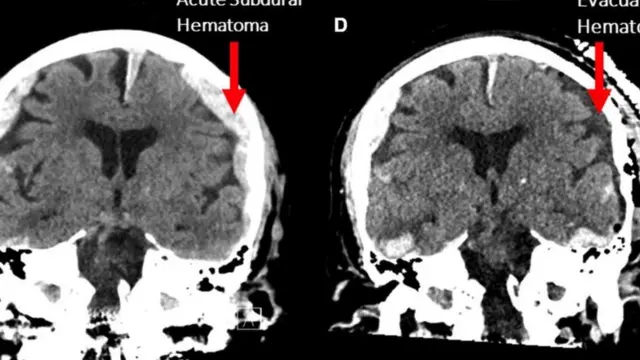

பட மூலாதாரம், Frontiers in Aging Neuroscience

நோயாளியின் இதயம் மூளைக்கு ரத்தம் கொண்டு செல்வதை வழங்குவதை நிறுத்துவதற்கு 30 வினாடிகளுக்கு முன்பு, அதிக அறிவாற்றல் தேவைப்படும் பணிகளான கவனக் குவிப்பு, கனவு காண்பது, நினைவுபடுத்துவது ஆகியவற்றைப் போன்ற பணிகளைப் பின்பற்றின என்று அவர் கூறுகிறார்.

எனினும் இந்த ஒரேயொரு ஆய்வில் இருந்து பரந்த, தீர்க்கமான முடிவுகளை எடுக்க முடியாது என்று ஸெம்மரின் குழு எச்சரிக்கிறது. ரத்தப்போக்கு மற்றும் வீங்கிய மூளை, வலிப்பு நோய் ஆகியவற்றை ஆய்வு செய்யப்பட்ட நோயாளி கொண்டிருந்தார் என்பதையும் கவனத்தில் கொள்ள வேண்டியிருக்கிறது.